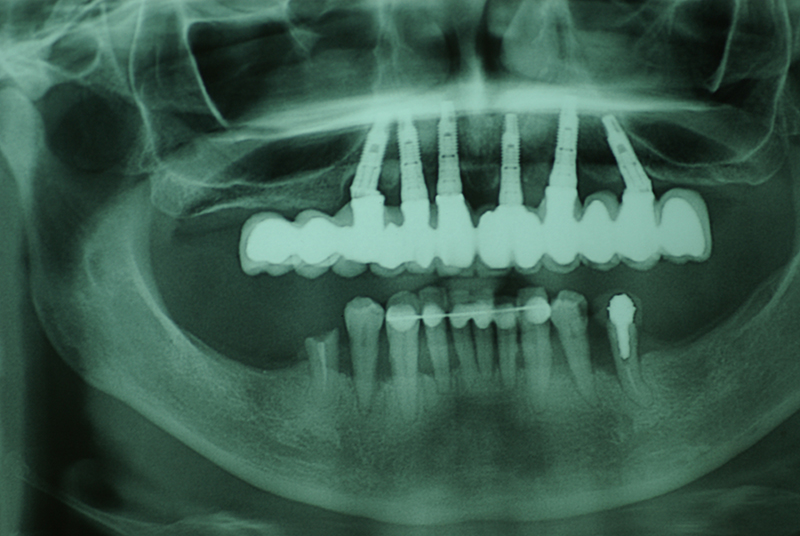

Na Clínica Pontes Odontologia, somos referência em implantes dentários em Fortaleza, oferecendo tratamentos de alta qualidade e tecnologia de ponta. Os implantes dentários são estruturas de titânio posicionadas cirurgicamente no osso maxilar ou mandibular para substituir as raízes dos dentes ausentes. Essa técnica permite a fixação de próteses personalizadas, restaurando a função mastigatória, a estética e a autoestima dos nossos pacientes.

Tecnologia CAD CAM para Maior Precisão e Conforto

Utilizamos a tecnologia CAD CAM, um sistema avançado que possibilita a confecção precisa das próteses dentárias diretamente sobre os implantes. Esse método inovador garante um ajuste perfeito, um resultado estético superior e proporciona muito mais conforto e durabilidade. Com o CAD CAM, nossos pacientes contam com um processo mais rápido e previsível para alcançar o sorriso desejado.